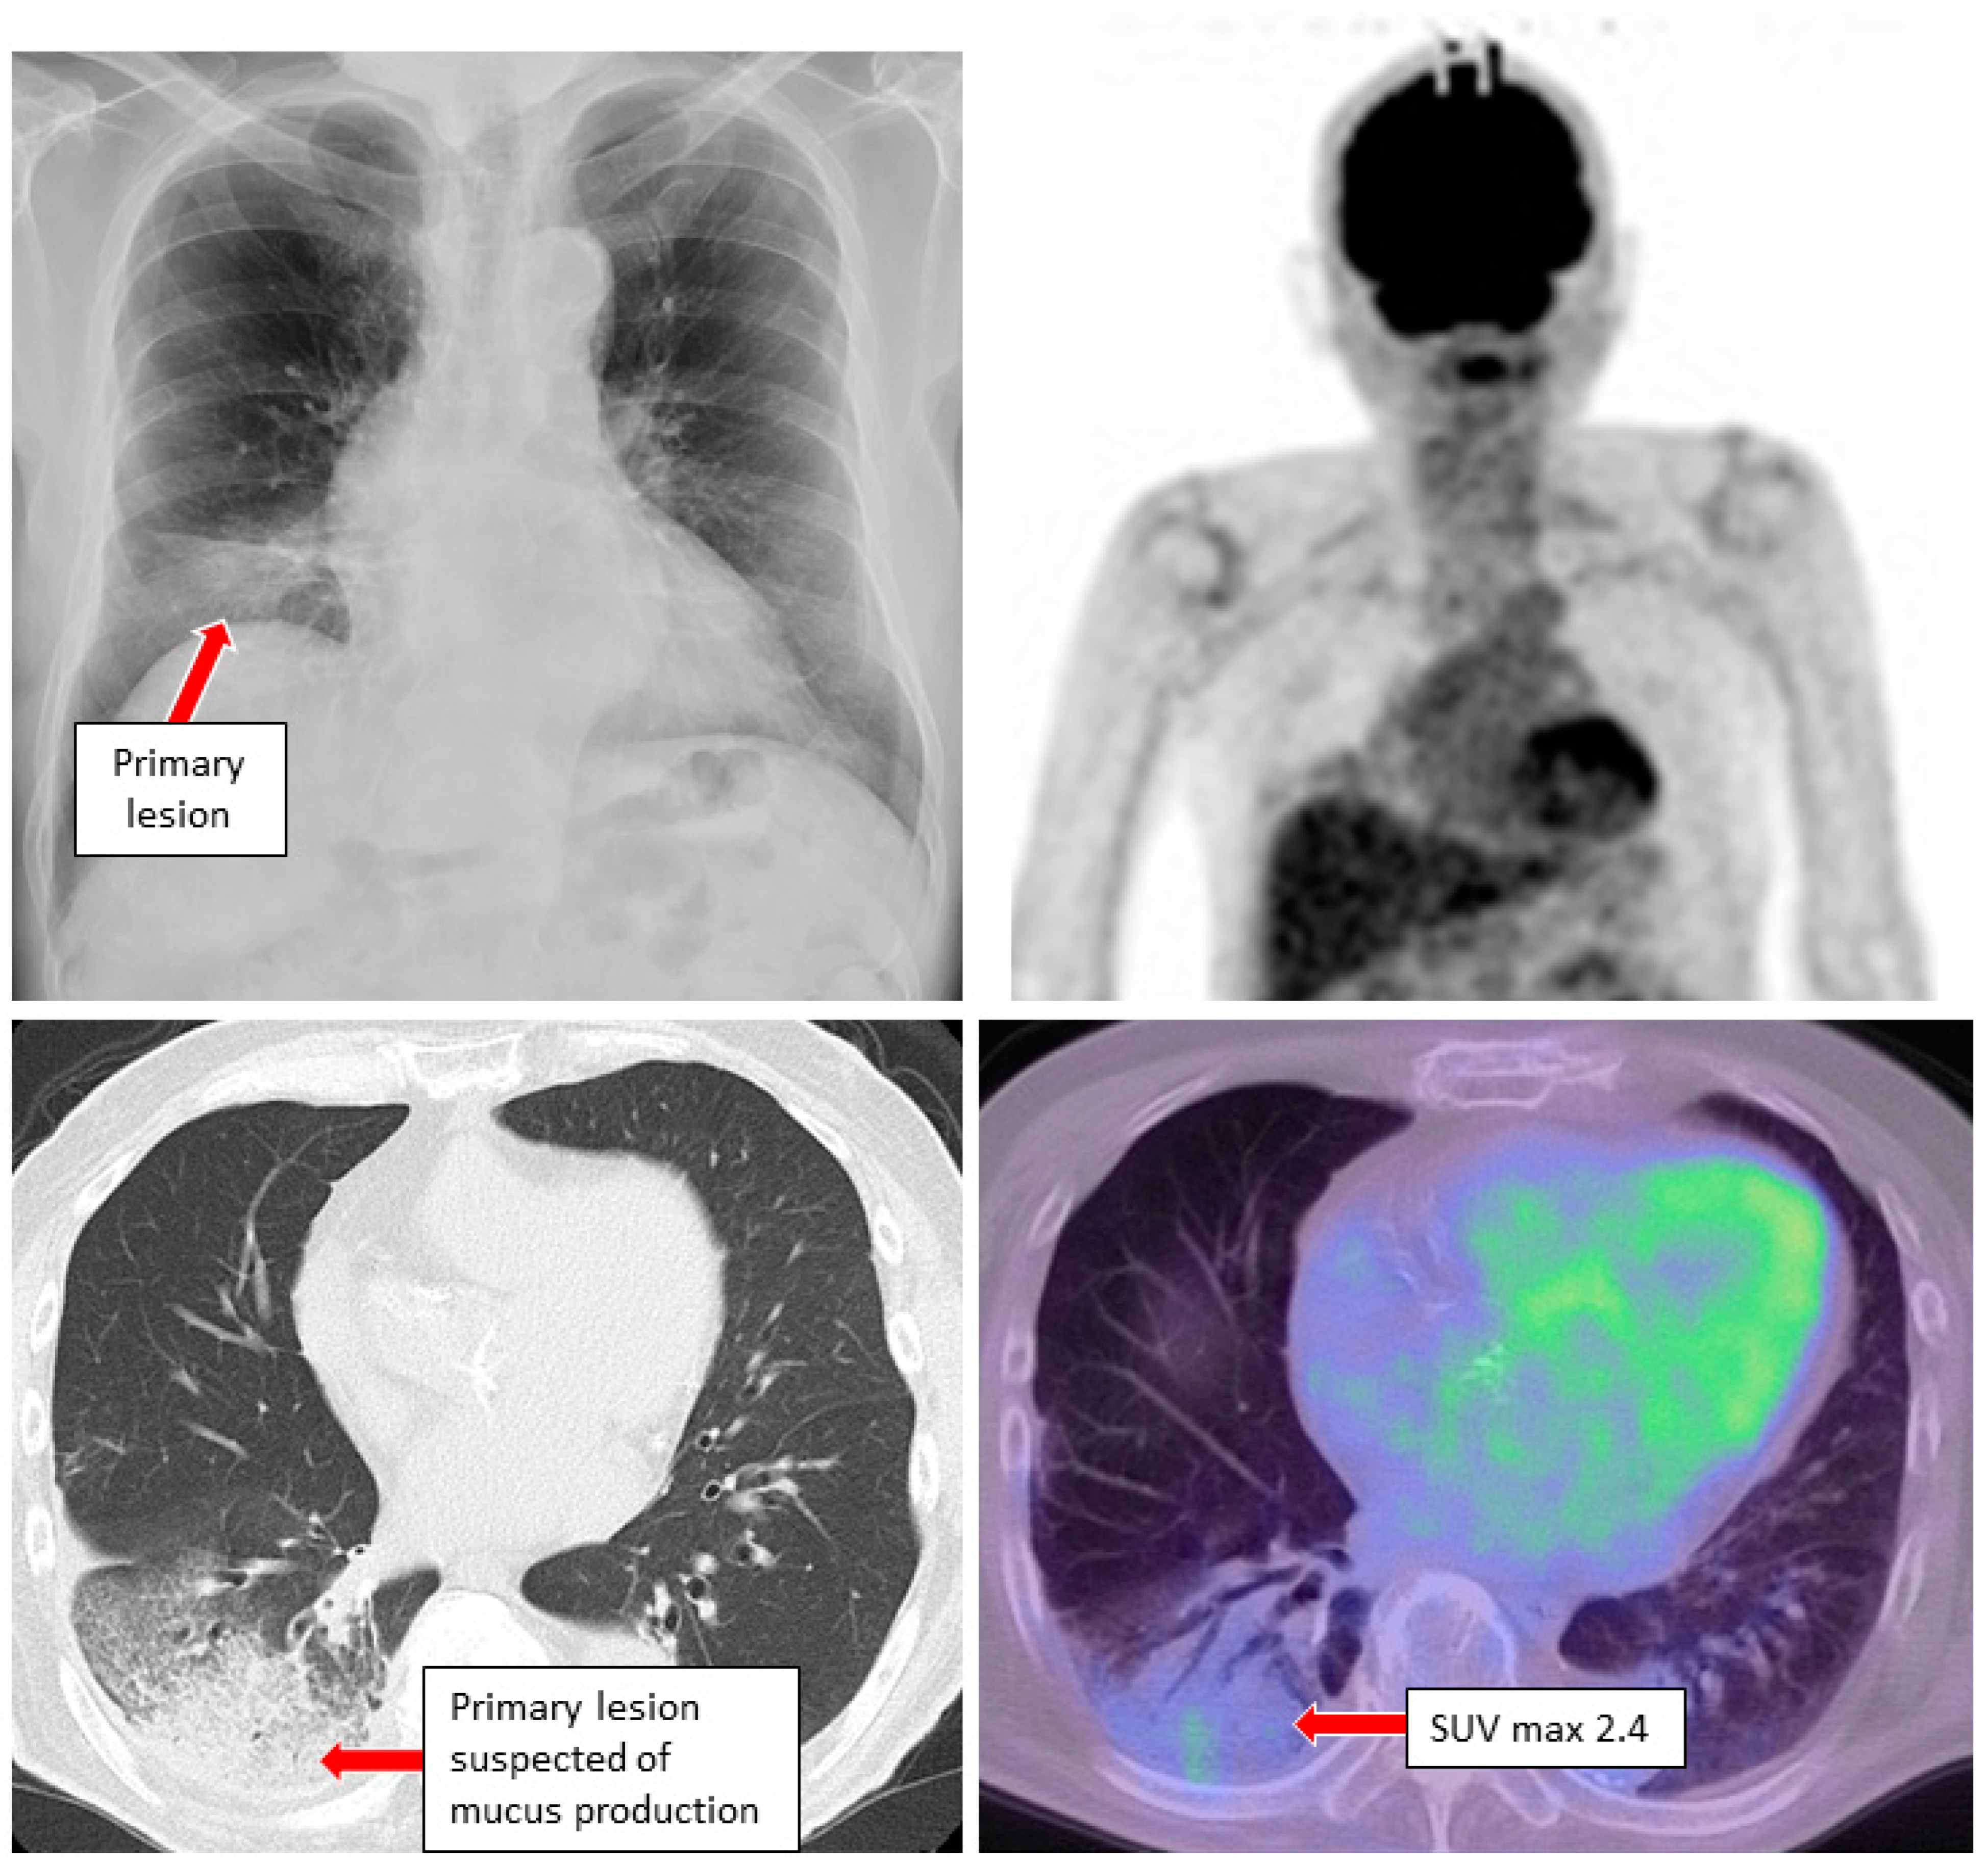

3. Case Reports